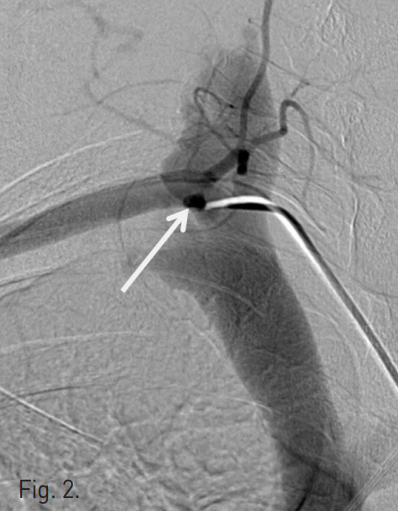

Fig. 1

Axial image of contrast-enhanced CT scan shows arteriovenous fistular tract (white arrow) between right subclavian artery (RSCA) and right internal jugular vein (RIJV).